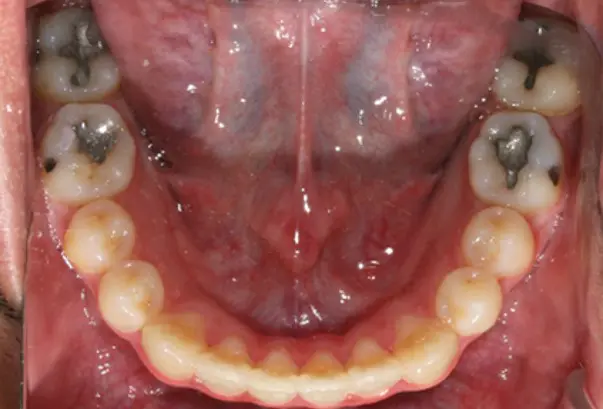

Crowding

After